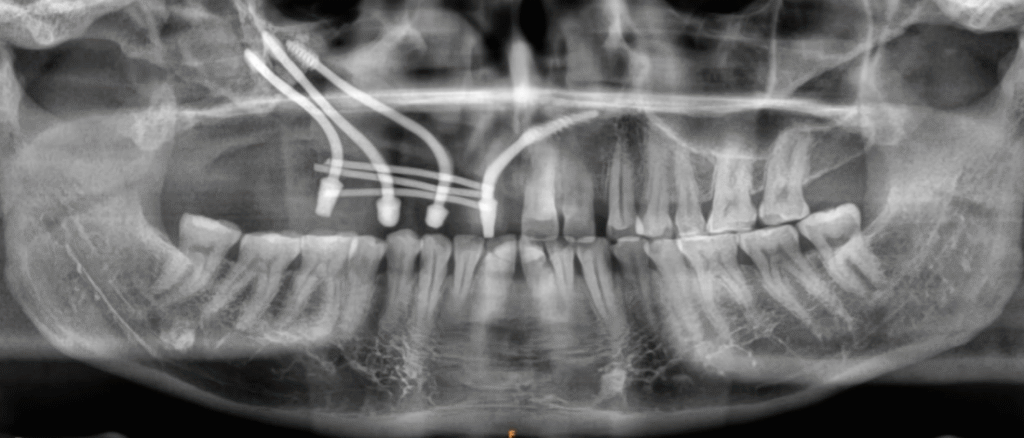

With the blueprint provided by the mock surgery, the team executed the final procedure with confidence. The implants were placed precisely as rehearsed:

- Three zygomatic implants,

- One anterior implant, securing sufficient support for a permanent prosthetic solution.

The patient’s treatment was ultimately a success — not by trial and error but through science, technology, and meticulous rehearsal.